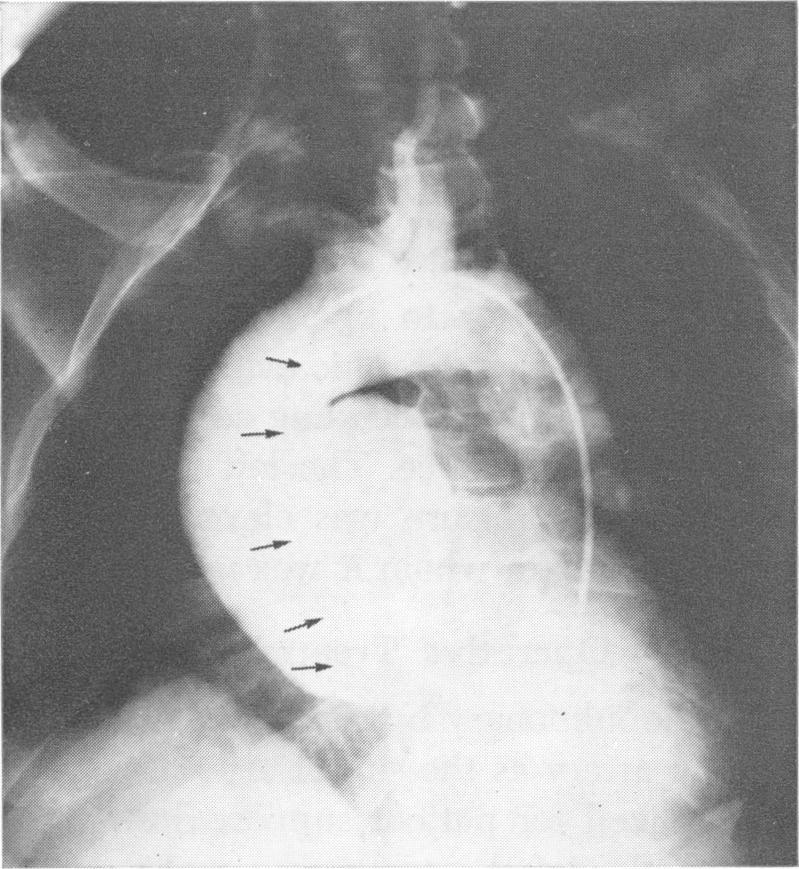

Killen D A, Collins H A, Sutton J P

Ann Surg. 1972 Jun;175(6):1017-23. doi: 10.1097/00000658-197206010-00021.